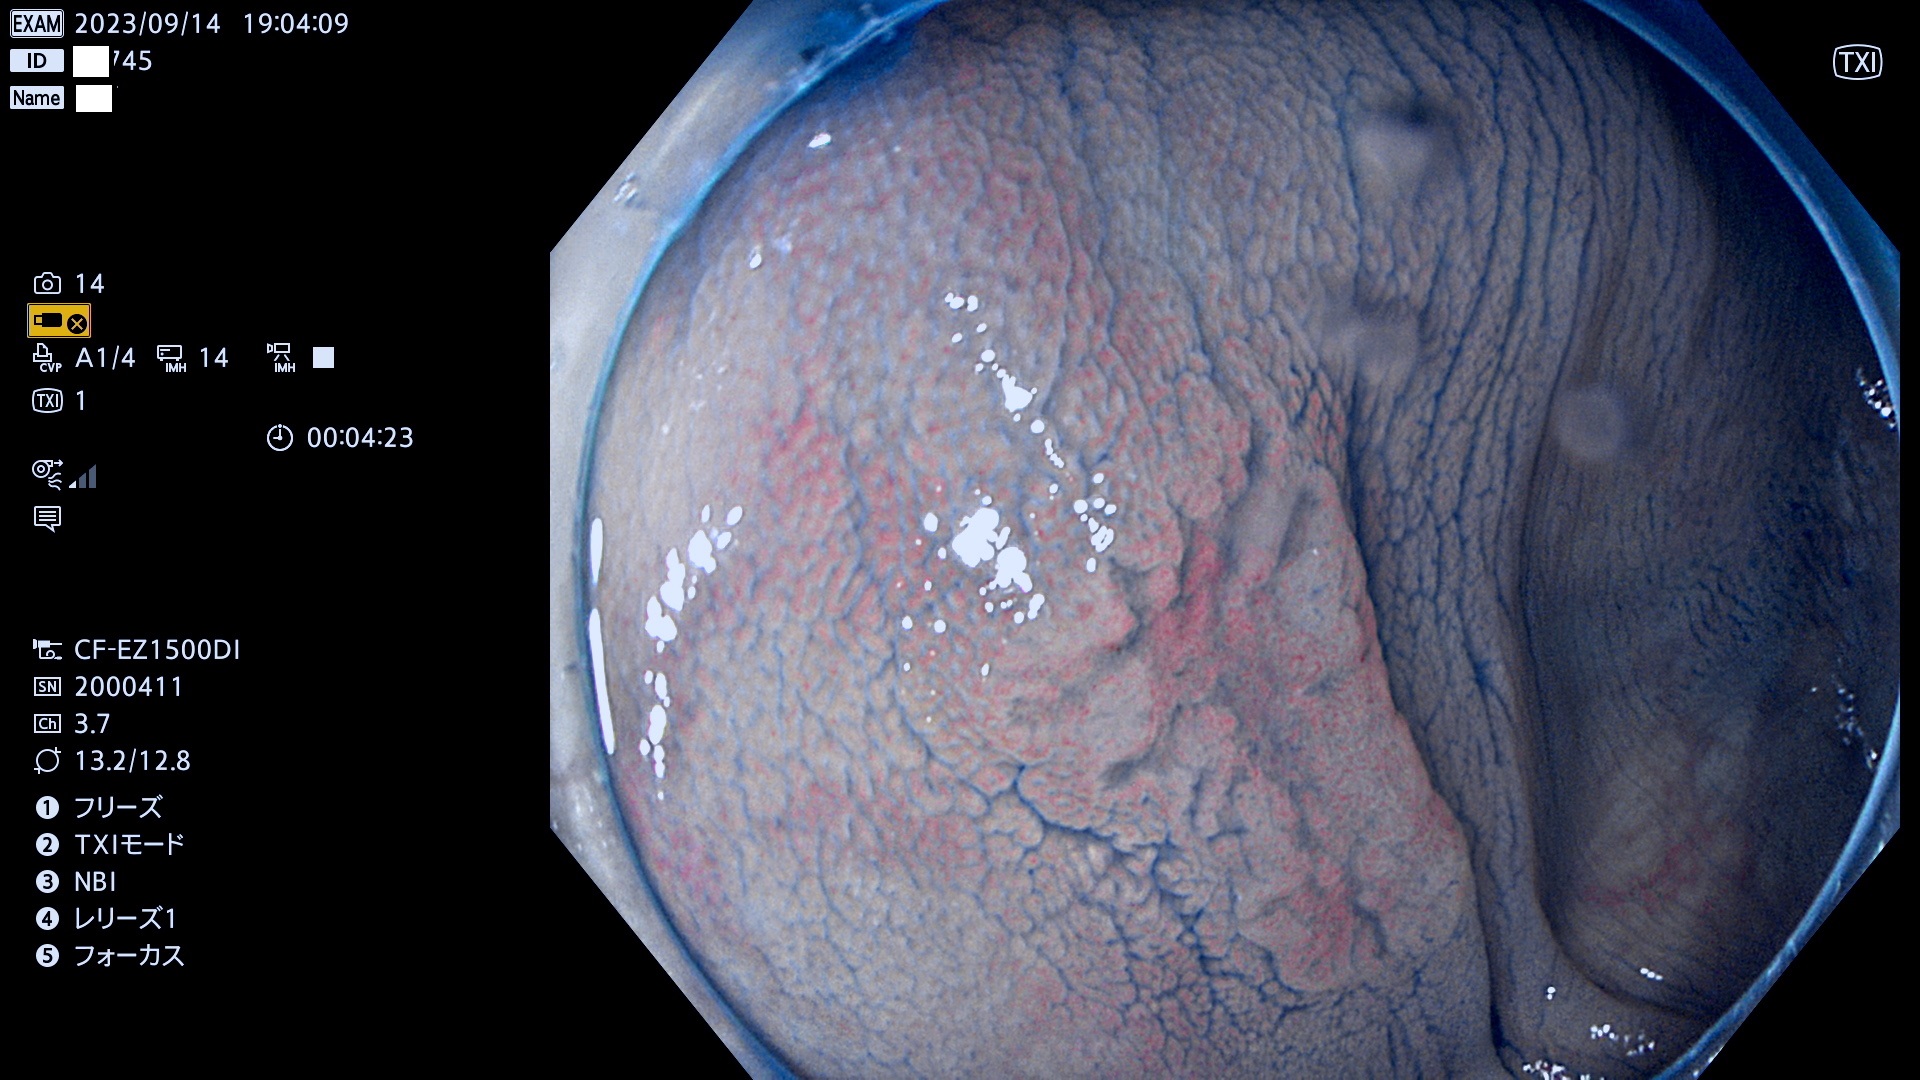

今週のUb、Uc型腺腫

表面型腺腫(Flat Adenoma)の中で、完全に平坦な物をUb、陥凹している物をUcと呼びます。平坦隆起型(Ua)よりも、発見が難しく危険な病変です。このタイプは「内視鏡後・大腸癌の重要犯人」であり、この発見率は「腺腫発見率」よりも、重要な意味があります。

毎週の検査(木・金・土・日)に発見されたUb、Uc型・腺腫を、その週の日曜の夜にUPし1週間、提示します。

抽出の対象期間 2023年9月14日(木)〜9月17(日)の4日間(48件の検査)7件